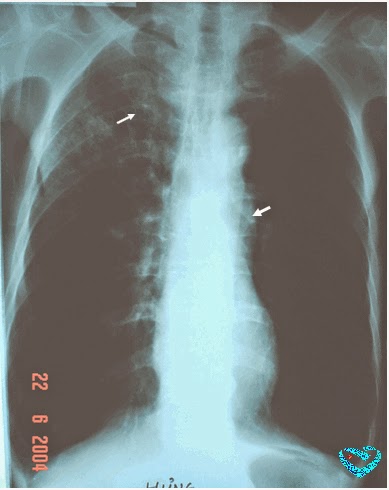

- Chụp X quang phổi: thường không nghi nhận dấu hiệu bất thường rõ rệt trên phim chụp X quang phổi. Có thể thấy một số dấu hiệu dày tổ chức kẽ phế quản xung quanh các mạch máu, phế quản, khi đó trên kết quả X quang phổi thường được ghi nhận dấu hiệu: “phổi bẩn”. Việc chụp X quang phổi là rất cần thiết giúp loại trừ các căn nguyên ho kéo dài do các bệnh có tổn thương ở nhu mô phổi (lao phổi, ung thư phổi, viêm phổi kẽ …) hoặc các bệnh lý phế quản như giãn phế quản …